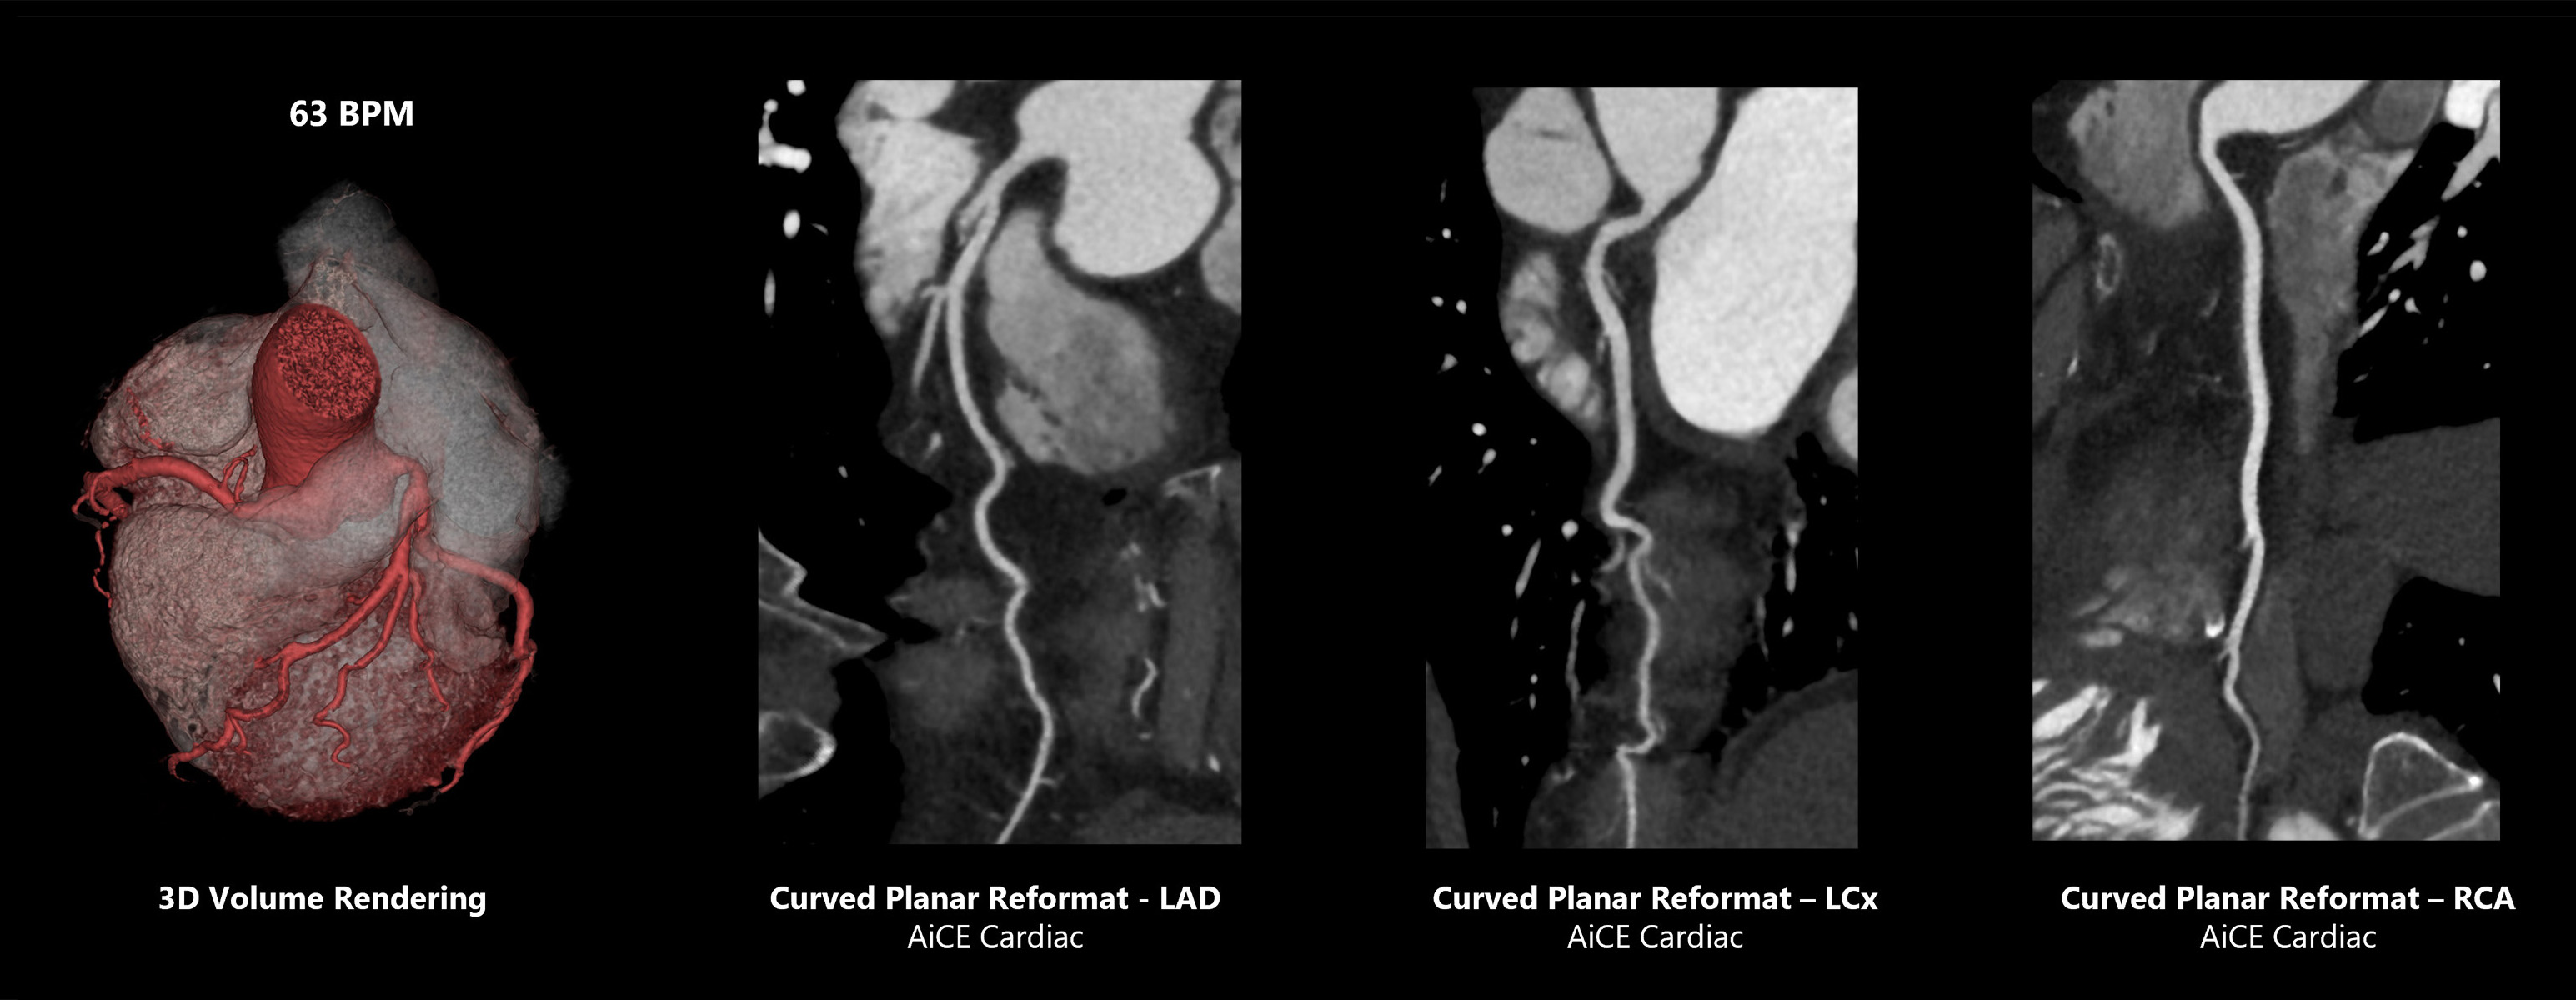

73 BPM Helical Gated Coronary Evaluation

Aquilion Serve SP

Coronary analysis on the Aquilion Serve SP with excellent temporal resolution and AI-power reconstruction with Advanced intelligent Clear-IQ Engine (AiCE) Deep Learning Reconstruction for sharp, clear, and distinct images improves consistency and diagnostic confidence.

View Scan Parameters| Scan Mode | kVp | mAs | Reconstruction | CTDIvol | DLP | Effective Dose† |

|---|---|---|---|---|---|---|

| Gated Helical | 135 | SUREExposure | AiCE | 65.7 mGy | 980.3 mGy·cm | 13.7 mSv |

† AAPM Report 96, k-factor 0.014

* Option

1 Global Illumination is a purchasable option, available in combination Vitrea® Advanced Visualization